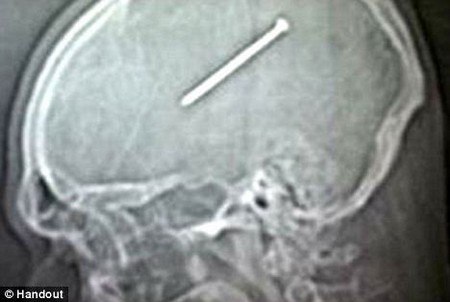

Một người đàn ông tại Mỹ đă vô t́nh bắn vào đầu ḿnh một chiếc đinh dài đến 9 cm bằng súng bắn đinh, tuy nhiên vẫn giữ cho chiếc đinh nằm trong đầu gần 2 ngày, trước khi quyết định đến bệnh viện để nhờ sự trợ giúp của bác sĩ.

Dante Autullo, 32 tuổi, đă vô t́nh bắn chiếc đinh vào đầu ḿnh bằng súng bắn đinh khi đang sửa lại căn nhà của ḿnh ở Chicago (Mỹ). Autullo tin rằng ḿnh đă vô t́nh nhấn vào nút bắn đinh khi đang đưa chiếc súng bắn ngang qua đầu ḿnh.

Chiếc đinh dài 9cm nằm trong đầu Autullo gần 2 ngày mà anh không hay biết

Hôn thê của anh, Gail Glaenzer, lập tức đưa Autullo đến bệnh viện gần nhất để kiểm tra. Tại đây, các bác sĩ đă hết sức bất ngờ khi kết quả chụp phim X-Quang cho thấy một chiếc đinh dài đang nằm giữa đầu của Autullo.

Rất may, vị trí của chiếc đinh chỉ cách phần chức năng kiểm soát vận động của năo bộ vài mm, do vậy Autullo vẫn có thể hoạt động b́nh thường sau khi chiếc đinh đi vào đầu.

Autullo đă lập tức được tiến hành phẫu thuật và các bác sĩ đă lấy chiếc đinh ra thành công sau ca đại phẫu kéo dài 4 tiếng. Các bác sĩ đă phải thay thế phần hộp sọ bị chấn thương của Autullo bằng hợp chất titan.